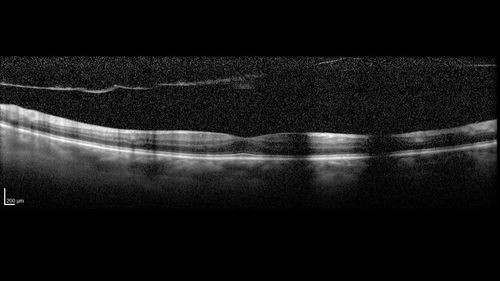

Vitreous Hemorrhage with no evidence of PDR in the left eye

74 year old man with vision loss OS for about a week. The FA shows no PDR in the left eye but the right eye has very mild NVD. Diabetes for 40 years now on insulin.